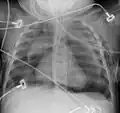

Pneumomediastinum is uncommon and occurs when air leaks into the mediastinum. The diagnosis can be confirmed via chest X-ray showing a radiolucent outline around the heart and mediastinum or via CT scanning of the thorax.

Pneumomediastinum and right sided pneumothorax post first rib fracture in a mountain biking accident. -

Pneumomediastinum with angel wing sign[15] -